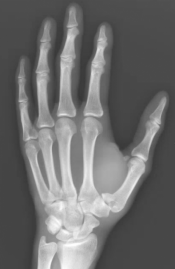

What’s the Diagnosis? Gepost op 1 oktober 2020 door netwerkvsseh What’s the Diagnosis? By Dr. Chris Smith @emdaily.cooperhealth.org Dit delen: Delen op X (Opent in een nieuw venster) X Share op Facebook (Opent in een nieuw venster) Facebook Delen op LinkedIn (Opent in een nieuw venster) LinkedIn E-mail een link naar een vriend (Opent in een nieuw venster) E-mail Afdrukken (Opent in een nieuw venster) Print Vind-ik-leuk Aan het laden... Gerelateerd